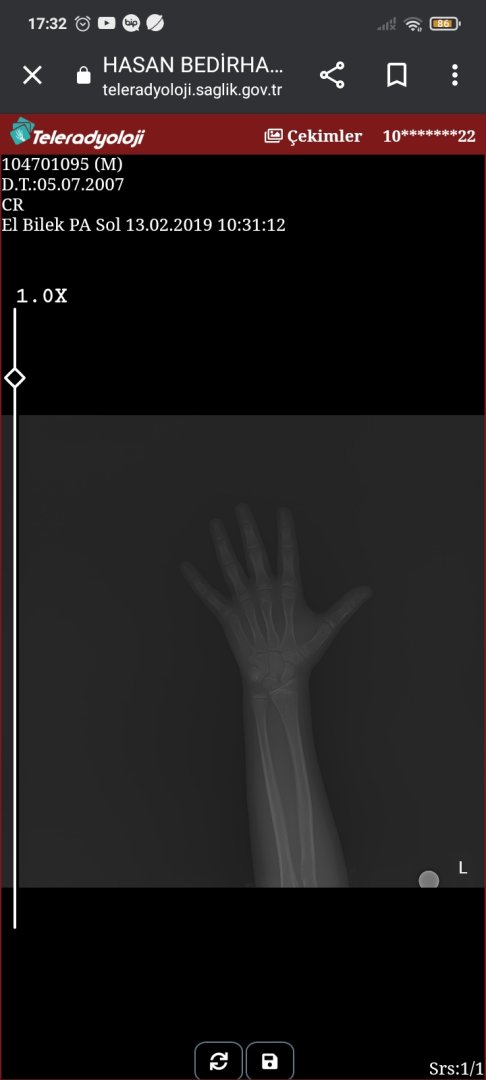

E nabızdan sol elimin röntgeni var kemik yasim nerede yazıyor nasıl anliyacagim?

Kemik fotoğrai

• Screenshot_2022-11-22-17-32-55-708_com.android.chrome.jpg